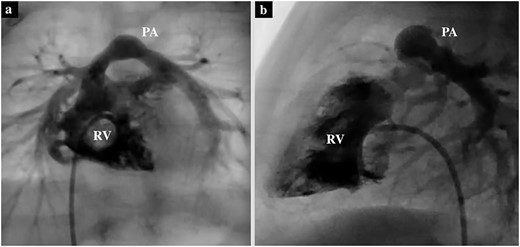

During the operation, the RCA could not be identified from the external surface. The main PA was incised longitudinally and extended into the right ventricular outflow tract along the AV groove between the RCA and the tricuspid annulus. The anterior leaflet of the tricuspid valve was identified during the right ventricular outflow incision, maintaining a distance of 3 mm from the tricuspid annulus to avoid approaching the RCA. The pulmonary cusps were highly fused, and pulmonary valve commissurotomy was performed. The right ventricular outflow tract was reconstructed using an expanded polytetrafluoroethylene (PTFE) monocuspid valve patch. While suturing the patch, only the endocardial side was sutured instead of all layers to avoid RCA injury (Fig. 4). The patient was discharged on postoperative Day 9. Six months post procedure, transthoracic echocardiography showed a trans-right ventricular outflow peak velocity of 1.4 m/s and moderate pulmonary valve regurgitation.

Intraoperative image of a monocuspid valve patch sutured to the PA and right ventricular outflow along the AV groove.